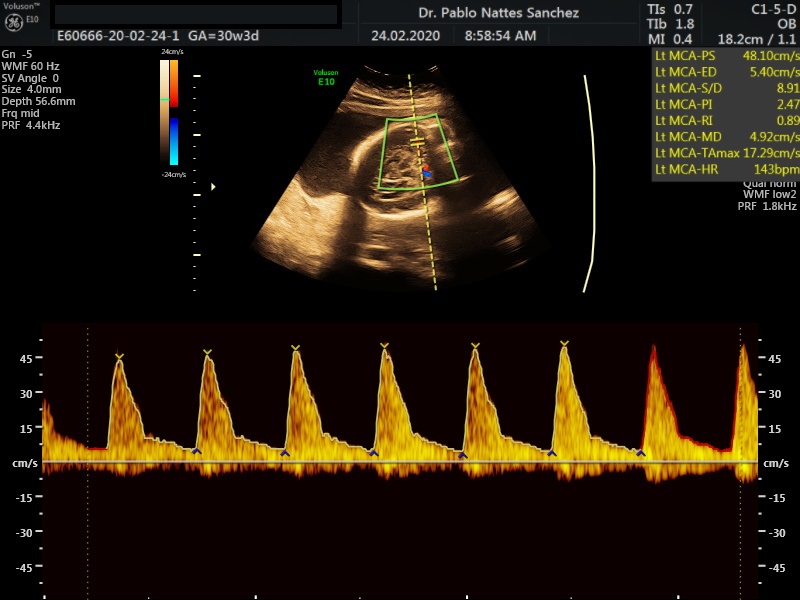

- La vitalidad y el bienestar fetal (Doppler).